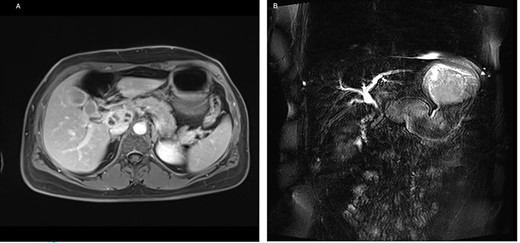

On admission, the patient seemed to be in good health, and her previous medical history contained no surgery. She reported pruritus, loss of appetite and weight loss of 5 kg in the past 3 months. Clinical examination showed slight epigastric tenderness and scleral icterus. Except for elevated liver function tests, the other blood tests, including tumor markers AFP, CEA and CA 19-9, were normal. For further assessment, we performed a magnetic resonance imaging of the abdomen, which confirmed the findings of the CT (Fig. 4).

(A) Axial-T1w view with contrast: findings correlating with the CT and (B) magnetic resonance cholangiopancreatography showing a signal interruption of the CBD due to obstruction.